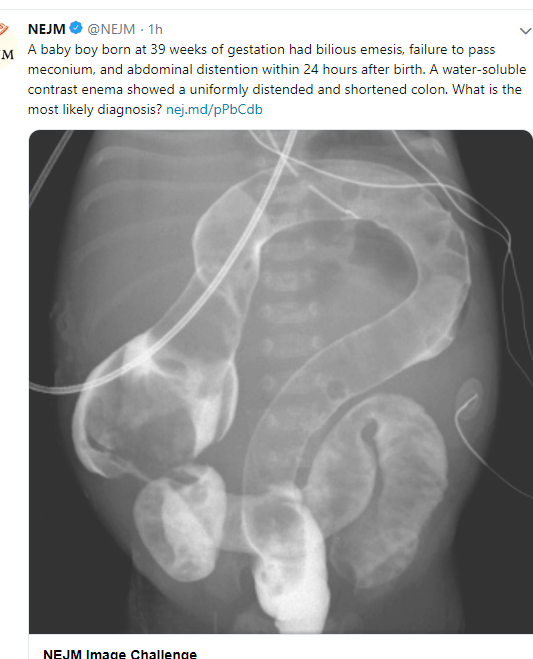

Hirschsprung’s disease:

• 1:5000 children.

• 100X higher risk in Down Syndrome.

• Prenatal testing not helpful at this time. There may be >360 genes that increase risk (variable degree of risk) of Hirschsprung’s disease; hence prenatal testing not that helpful at this time.

• 30 associated genetic syndromes with Hirschsprung’s, >12 known gene defects.  Hirschsprung’s disease: 25% with RET haploinsufficiency.  RET haploinsufficiency –increases risk of Hirschsprung’s disease >2500-fold risk.